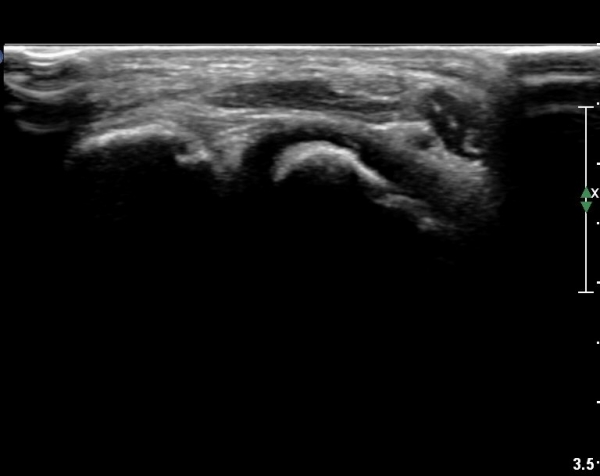

ÃÊÀ½ÆÄ °Ë»ç